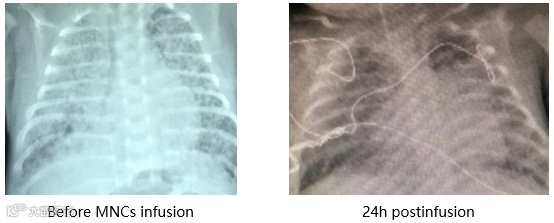

2. 胎龄25+w,外院诊断重度BPD,生后120天仍未能撤离呼吸机入院。

输注脐带血后气道高反应性缓解。